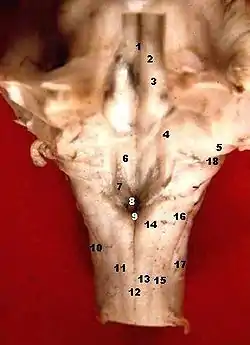

Human caudal brainstem posterior view (Dorsal cochlear nucleus is #5)